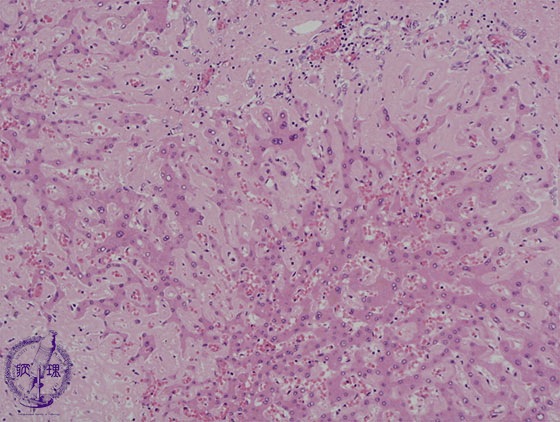

Microscopic image (HE stain, high power): There is deposition within sinusoids of a pink amorphous material (amyloid) and hepatocytes are atrophic.